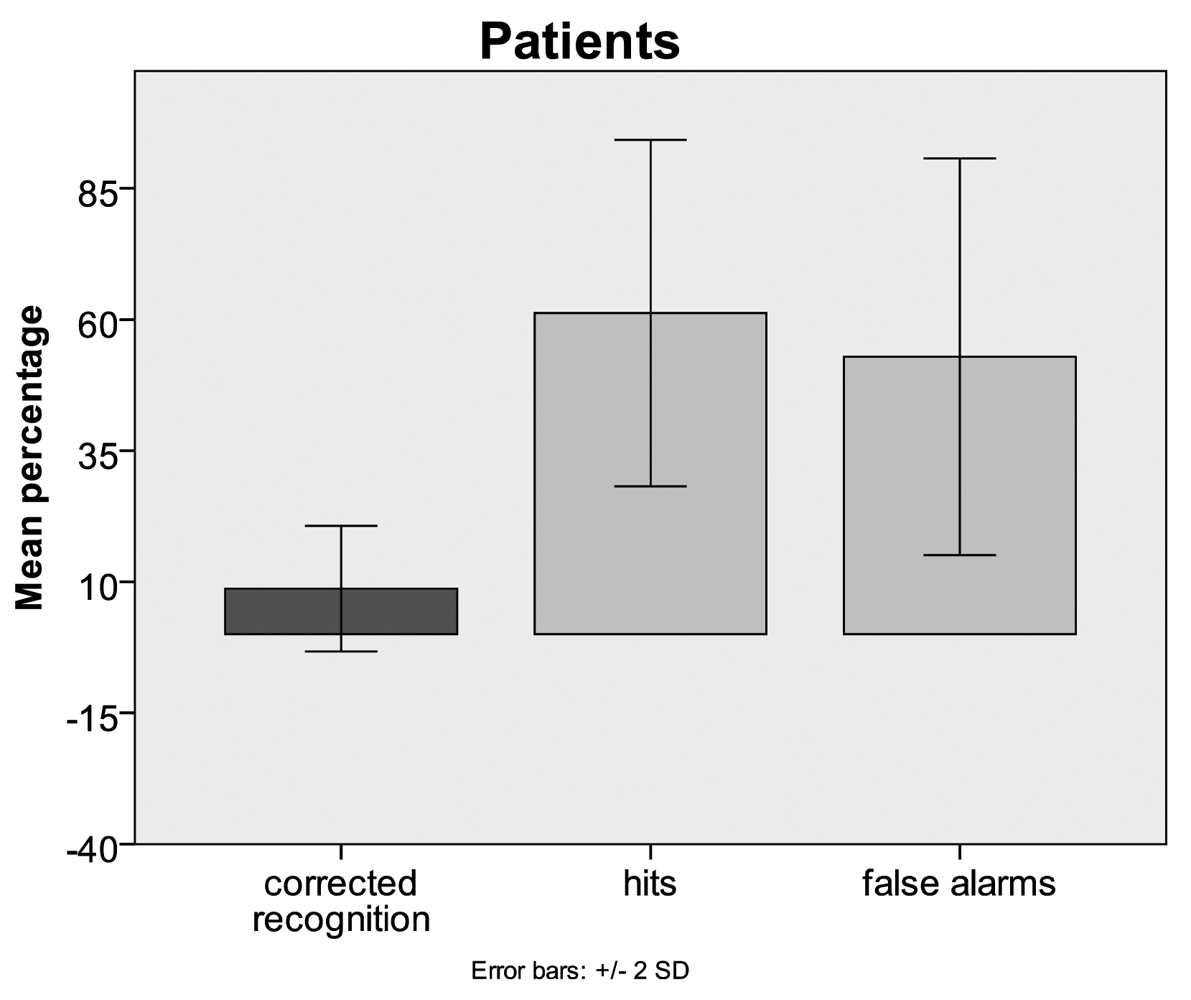

3.1. Behavioural Data

4.1. Behaviour